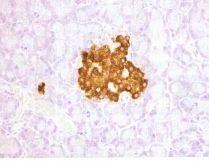

免疫組織化學染色法(DAB顯色)2.辨認細胞產物的來源。利用某些細胞產物為抗原,製備相應的抗體,對組織細胞實施免疫組織化學染色,以確定細胞產物的來源。如內分泌細胞產生的各種激素,大多數可用免疫組化染色技術辨認,據此可研究細胞的分泌功能及對內分泌腫瘤作功能分類,檢測分泌異位激素的腫瘤等,了解細胞分化程度。